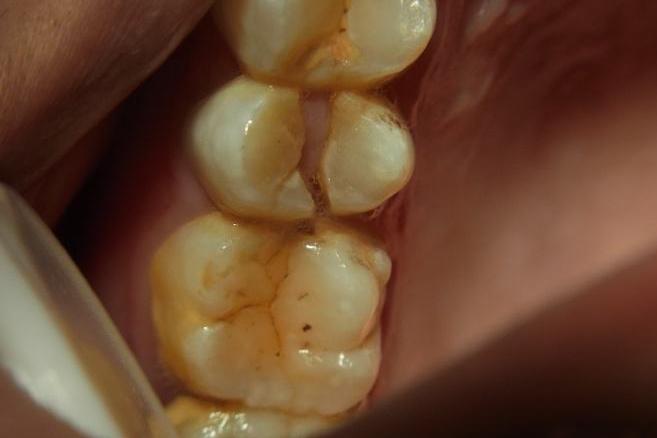

经过检查,发现这位患者牙齿完全劈裂,无法保留,只能拔除。

劈裂的牙齿

大家平时照镜子时,仔细看会发现牙齿上会有一些细微的裂纹,有些裂纹只是表面的纹路,不会有任何症状,也无需进行治疗。而有些时候,裂纹就像隐形的“杀手”一样,不注意的话就可能给牙齿带来不可逆转的损伤。

同时牙隐裂典型的症状是较长时间的咀嚼不适或咬合痛,这种疼痛可能长达几个月甚至几年。所以当某一固定牙位置的反复咬合痛,就需要特别注意了,稍不注意,牙齿甚至会沿着裂纹完全劈开。